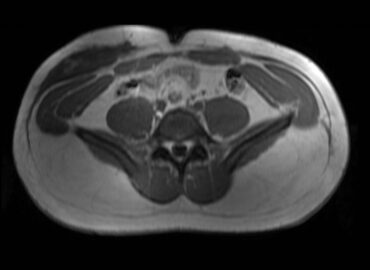

Paciente masculino, 32 años que consulta por tumoración a nivel de partes blandas localizado en flanco y FID. […]